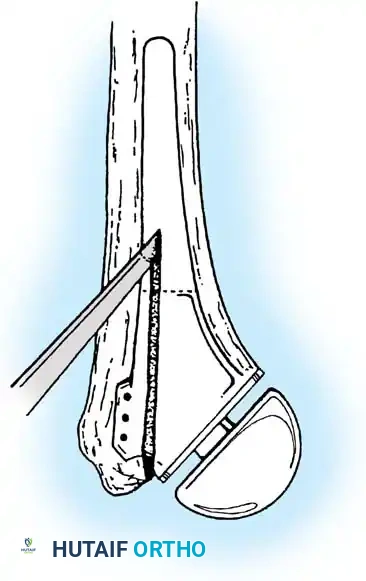

3. Humeral Head Resection

Dislocate the humeral head anteriorly through external rotation and extension. Remove peripheral osteophytes to identify the true anatomical neck. The humeral cut is made along the anatomical neck, typically at 30 degrees of retroversion and 45 degrees of inclination.

5. Humeral Preparation and Implantation

Broach the humeral canal sequentially. Assess the trial components for stability, ensuring 50% posterior translation on the "drawer test" and no superior escape. Implant the final prosthesis (press-fit or cemented based on bone quality).